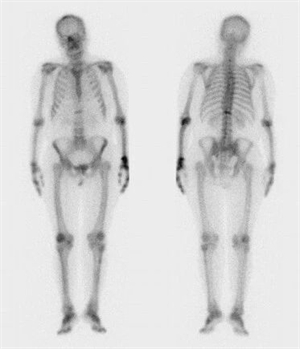

全身骨骼显像检查有个通俗名,叫“骨扫描”,原理其实特简单,就3步:

1.打“追踪器”:先注射一点点显像剂(常用的是99mTc-MDP),它会跟着血液跑遍全身骨骼;

2.等一等:注射后歇2-6小时,让“追踪器”在有问题的骨头里“聚堆”——哪里有损伤、有转移,它就往哪去;

3.扫一圈:用专门的仪器(SPECT)扫10来分钟,就能看到骨头的“发光图”——亮的地方就是病灶,像张阿姨的椎体骨折,一扫就显形了。

更省心的是,它能“一次查遍全身”:不用分部位反复扫,注射一次显像剂,从头到脚的骨头都能看清楚,不管是肿瘤转移到骨头。还是像张阿姨这样的隐匿骨折,都逃不掉。